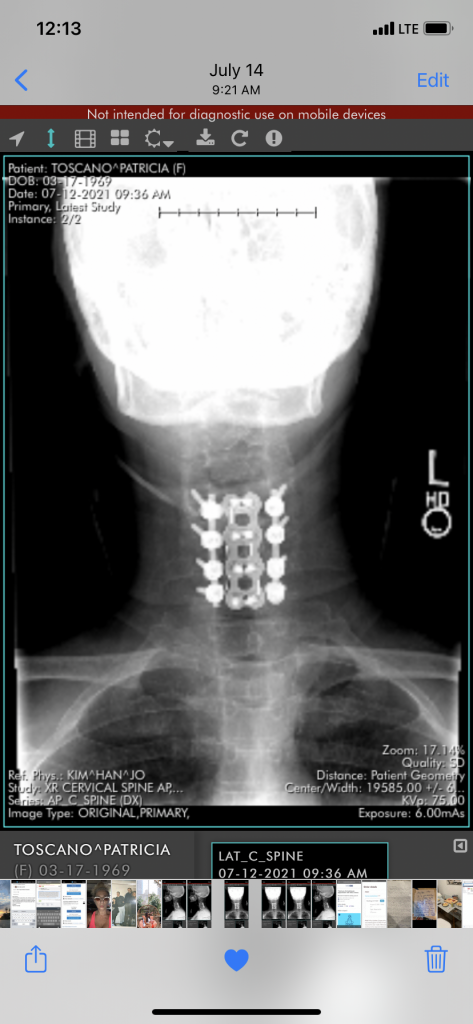

Spinal Fusion Surgery

I had been paralyzed in February, and was in a speechless place for three days! I was saved by Dr . Kim! He was the only doctor to make a blessed decision to save my life! With the help of the hospital staff as well as a social worker, it was all made possible! I’m stronger then ever! A true miracle! Thank you Dr. Kim! I don’t know the words to express the grateful breath I wake up to everyday! I have joy in my heart every breath I take I’m grateful for you. You gave me my active life just like you said! Dr. Kim is a godsend! Truly a beautiful soul of a human being! I’m off pain medication after 8 years of a cervical spine problem with nerve and brain injury! Dr Kim fixed a percentage of it I feel. I truly have a beautiful journey forward.

This experience has been severely traumatizing for me. I believe I truly have my life back because Dr. Kim is a loyal soul of a doctor! Blessed to have you in my heart for the rest of my days. Yesterday was 6 months from my surgery, and I will do my best to stay active. It feels wonderful to have no pain, as there are many challenges with the nerves that trigger brain issues. I’m so much better. I have about 6 months to pay attention, and it should get better as the days go by. The cold is being a problem, so I’ll stay home this winter. Blessed to be alive! I’m on a journey one day at a time. Dr. Kim saves! Thank you!❤️